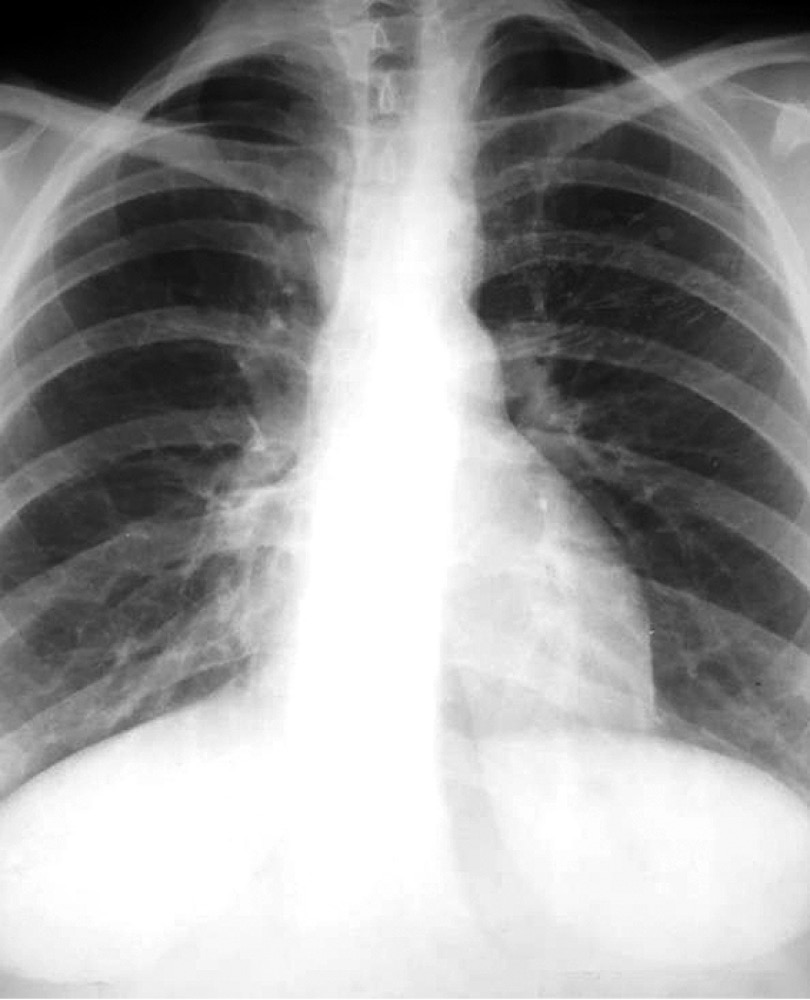

Из анамнеза известно, что больная в течение двух последних месяцев стала отмечать появление одышки при физической нагрузке. Состояние ухудшалось, дополнительно появились отёки на лице к вечеру. При обращении к участковому терапевту в поликлинику по месту жительства выполнена рентгенография грудной клетки, в результате выявлено массивное опухолевое образование в средостении (рис. 1, 2).

Рис. 1. Рентгенография грудной клетки в прямой проекции.

Fig. 1. X-ray of the chest in direct projection.